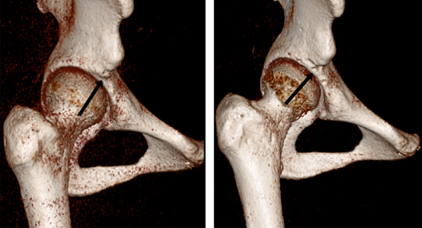

近年来我所已开展针对成人髋关节发育不良的保髋治疗。目前髋关节组已开展髋臼周围截骨术、股骨去旋转截骨术近五十例,包括专业运动员3例,近期随访效果满意。同时,髋关节组在国内率先开展了髋关节镜联合髋臼周围截骨术,首先利用髋关节镜下将关节内的盂唇及软骨损伤进行修复,然后通过髋臼周围截骨手术改善患者的髋臼覆盖情况。本手术方式可以更好地提高患者的手术疗效。这丰富了我所髋关节疾病的治疗手段,极大推动了髋关节专科的学科发展。